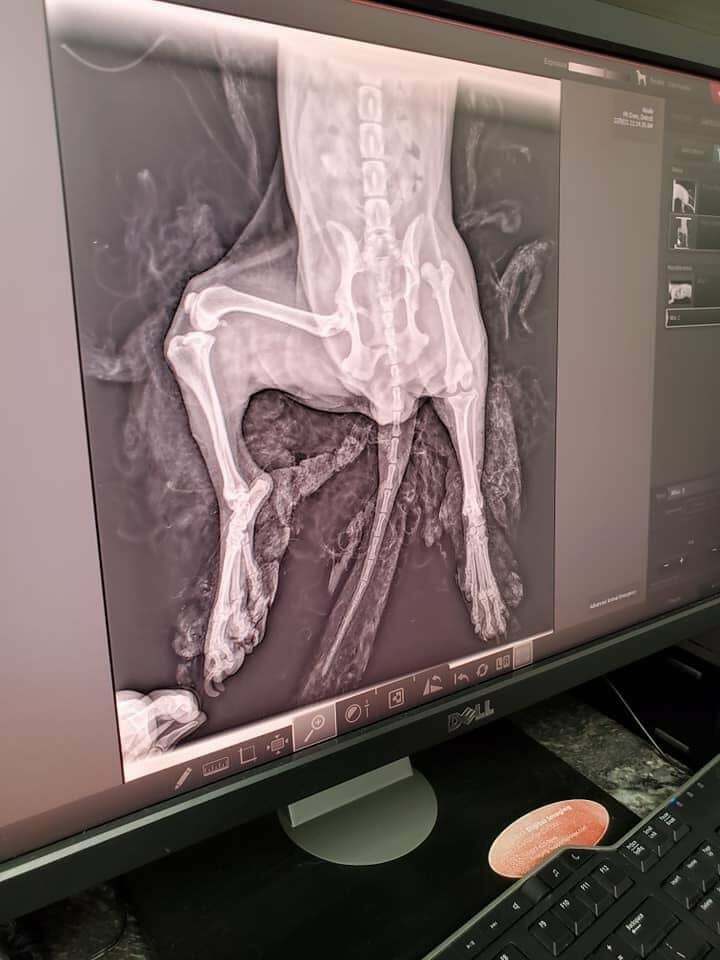

🐾❤NOEL UPDATE❤🐾